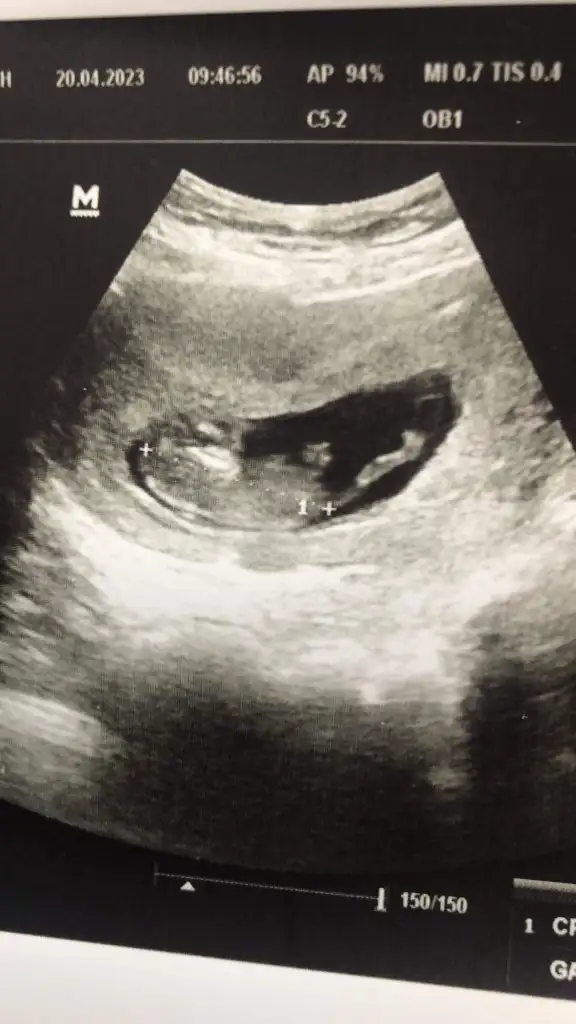

Bu bacak arası evet. Benim de ilk erkek olarak söylemişti doktorum sonra kız oldu. Hala tereddütteyim ben de. Detaylıya kadar bekliyoruz o yüzden :)Ya arkadaşlar bebeğim 16 haftalık bugün 4 lü tarama için gittim 16 hafta boyunca bebeğe erkek diyen doktor bugun de kıza benziyo dedi şaştım kaldım nasıl öğrencem ben cinsiyeti doğru hangisi ? EKLEDİĞİM GÖRSELDE BACAK ARASINI MI ÇEKTİ BİLMİYORUM BAKAR MISINIZ

16 haftaya kadar her gittiğimde erkek çıkıntısı var dediler 16. Haftada kız dedi doktorKız gibi canım bana öyle geldi çünkü erkek de çıkıntı hemen belli oluyor bunda hiç çıkıntı yok ve 16. Haftaya kadar çok çok daha belli olurdu

16 haftaya kadar bacak arasını görerek mi çıkıntı var dedi? Yoksa yandan mı bakıyordu? Birde 16.haftada bacak arasına baktığında üç çizgiden bahsetti mi?16 haftaya kadar her gittiğimde erkek çıkıntısı var dediler 16. Haftada kız dedi doktor

Üç çizgi falan hiç bahsetmedi sadece bacak arası boş dedi16 haftaya kadar bacak arasını görerek mi çıkıntı var dedi? Yoksa yandan mı bakıyordu? Birde 16.haftada bacak arasına baktığında üç çizgiden bahsetti mi?

Evet bendeCanım bana da kız gibi geldi bebeğimin cinsiyetini çok merak ettiğim için bununla ilgili 1000 tane video izledim, erkek bebekte çıkıntı kız bebekte 3 tane çizgi oluyor böyle yan yana :)